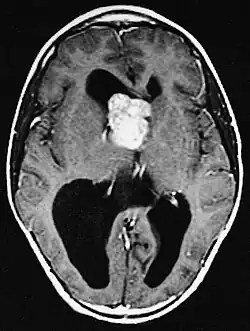

Fehlbildungen und Tumoren des Gehirns

Fehlbildungen und Tumoren des Gehirns werden oft frühzeitig festgestellt. Kortikale glioneuronale Hamartome, die so genannten Tubera (Vorwölbungen) im Bereich der Hirnrinde, gehen häufig mit Epilepsie einher und können kognitive Beeinträchtigungen verursachen, während subependymalen Riesenzellastrozytome und subependymale Knötchen aufgrund ihrer Nähe zum Ventrikelsystem typischerweise zur Entwicklung eines Hydrozephalus führen.

Eine ursächliche Therapie der tuberösen Sklerose gibt es derzeit nicht, die Behandlung beschränkt sich auf die Symptome, insbesondere auf die der Epilepsie. Zur Therapie der Fehlbildungen und Tumoren des Gehirns stehen neben neurochirurgischen Optionen inzwischen auch immunsuppressive Medikamente mit Hemmung der mTOR-Signalkaskade zur Verfügung.[14] Viele Menschen mit gering ausgeprägter tuberöser Sklerose führen ein weitgehend normales Leben. Bei stärkerer Ausprägung kann die Lebenserwartung insbesondere bei schwerer Epilepsie, ausgeprägten kognitiven Beeinträchtigungen und durch das Auftreten von Tumoren jedoch begrenzt sein.